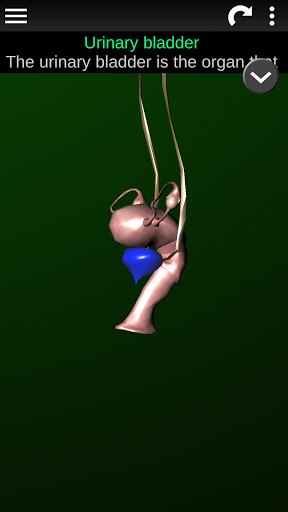

* Описи кожного органу.